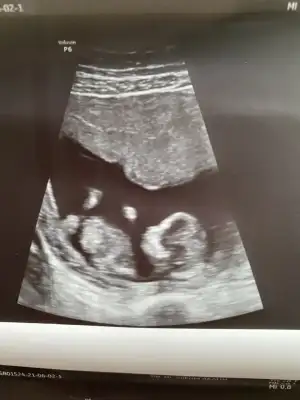

Net değil USG başka USG varsa paylaşın

Yenisi ekledimNet değil USG başka USG varsa paylaşınkız sanki emin olamadım

Kız görünüyorYenisi ekledim![]()

Kız gibi sanki daha önceki karanlık USG emin olmamıştımBen bugün gene kontroldeydimIkra meyra her seferin farklı tahminde bulunuyor ama bugün met ve emin söyledi. Bakalım sen ne diyeceksin? Bemce poposu dönük ama öyle bişey demedi.

Evet bu sefer de kız dedi kesin konuştu ama ben 20. Hafta detaylıyı beklecepim emin olmak için. Teşekkür eserimKız gibi sanki daha önceki karanlık USG emin olmamıştım

Kız gibi sanki

En iyi 11 12 13 haftalar olmalı şimdilik kız yönünde ama yanıltabilirIkra meyra bana da yorum yapar mısın cinsiyet için